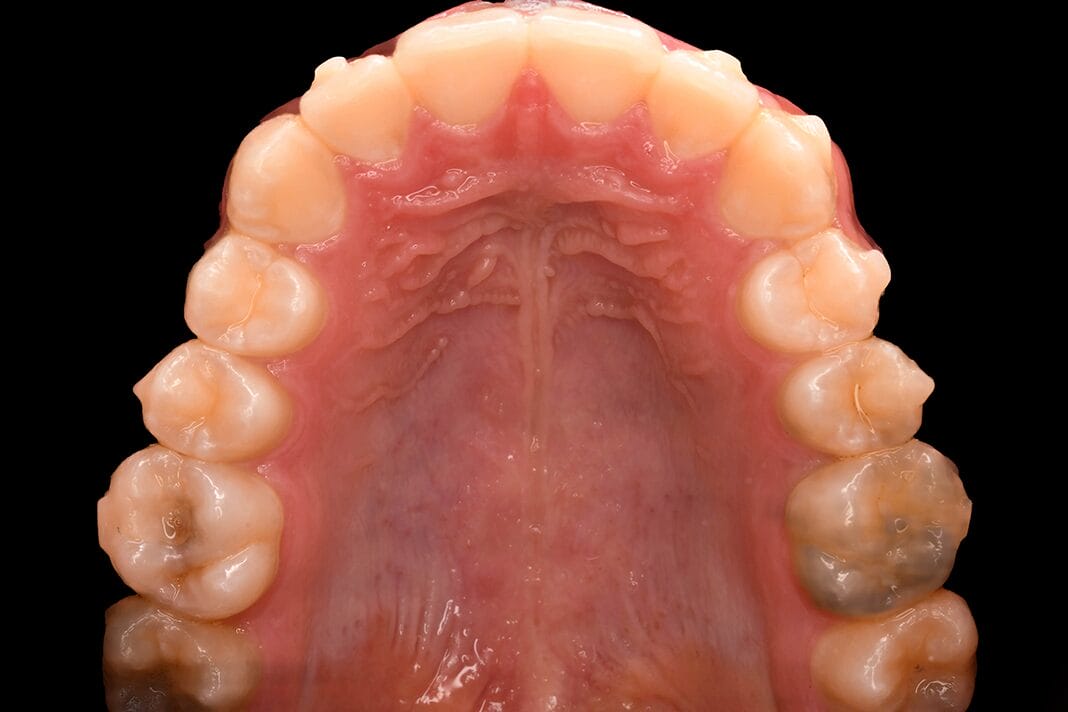

Additionally, one of the postoperative complications of osteotomy is sensory disturbances of the maxillary teeth, though these complications are often not long-term. Could this mean there is an alternate nerve supply for the maxillary teeth? The consensus is that the greater palatine nerve and artery supply the palatal mucosa, gingiva, and glands, but not the bone or tooth adjacent to those tissues. However, there are multiple small foramina visible, when closely observed, on the palatal surface of the alveolar process.1

This begs the question: What is the function of the small foramina on the palate?

The results showed that the alveolar branches of the greater palatine nerve and artery also supply the maxillary teeth via small foramina in the palate, groove, and even the greater palatine canal.1

The colored water injected into the small foramina became visible in the socket adjacent to the small foramina. This was observed from the incisor to the third molar on all sides. Similarly, the latex injected into the alveolar sockets was observed emerging from the small foramina on the palate.1

These findings suggest communication between the alveolar socket and the small foramina on the palate, indicating that the nasopalatine nerve and the sphenopalatine artery supply the maxillary teeth, most likely the anterior maxillary teeth, while the greater palatine nerve and artery most likely supply the maxillary molars.1

Gross dissection revealed the greater palatine nerve and artery, and their branches travel through the groove on the alveolar process to enter the bone via small foramina. This was true for the greater palatine nerve branch and the greater palatine artery branch, both in some areas.1

Histological observations through coronal sections indicated that the small foramina in the first molar area contain a small nerve and artery.1